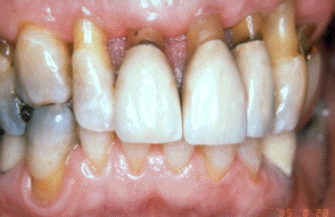

Mujer de 60 años de edad  que ha desarrollado  enfermedad periodontal severa. Las profundidades de las bolsas al sondaje son de 5 a 8 mm y el examen radiográfico muestran que aproximadamente 50%  del hueso alveolar se ha perdido en el maxilar  superior. Las encías superiores muestran signos de inflamación severa.  Los rasgos clínicos no permiten un análisis de la anatomía de la destrucción periodontal.